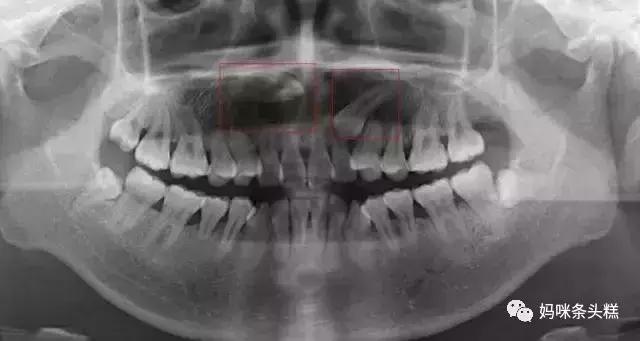

在遇到这类问题时,医生会选择给宝宝拍片,确定埋伏在牙床中未萌出的恒牙到底遭遇了什么情况。

有的并不是恒牙缺失,但恒牙萌出角度偏差,又遇到相邻牙齿的阻力导致无法萌出,这时需要根据牙齿与牙齿间的间隙空间情况,决定是否需要拔除阻生牙齿,让恒牙正常萌出。

拔除后除了提供恒牙正常生长的间隙,还会需要根据牙齿埋伏的深浅程度决定是否需要进行恒牙牵引,帮助萌出。